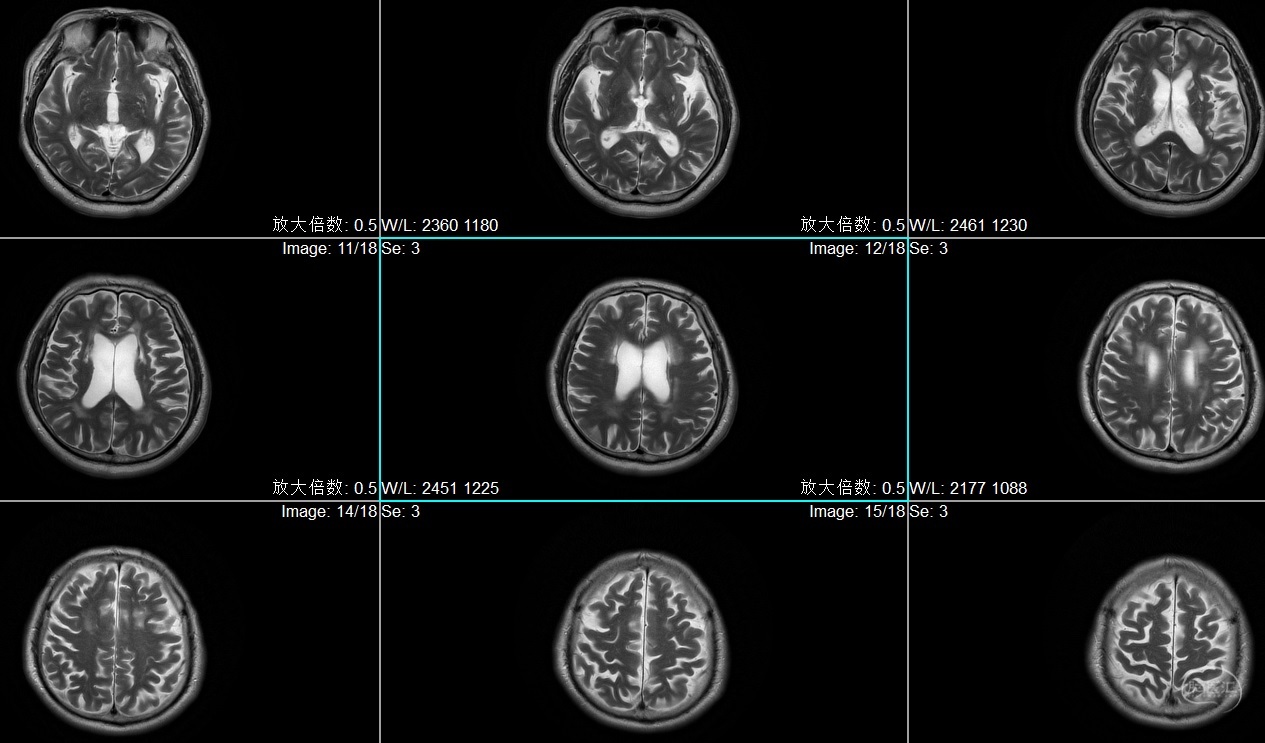

患者李XX,男性,63岁,主因右肢无力1月入院

既往高血压病史,糖尿病史,脑梗死病史5年,遗留优质活动不利,冠心病病史

查体:BP:129/75mmHg,神情,言语正确,四肢从嘱,GCS:15分,双侧瞳孔各3mm,对光反射灵敏,右侧肌力4级,左侧5级

患者李XX,男性,63岁,主因右肢无力1月入院

既往高血压病史,糖尿病史,脑梗死病史5年,遗留优质活动不利,冠心病病史

查体:BP:129/75mmHg,神情,言语正确,四肢从嘱,GCS:15分,双侧瞳孔各3mm,对光反射灵敏,右侧肌力4级,左侧5级